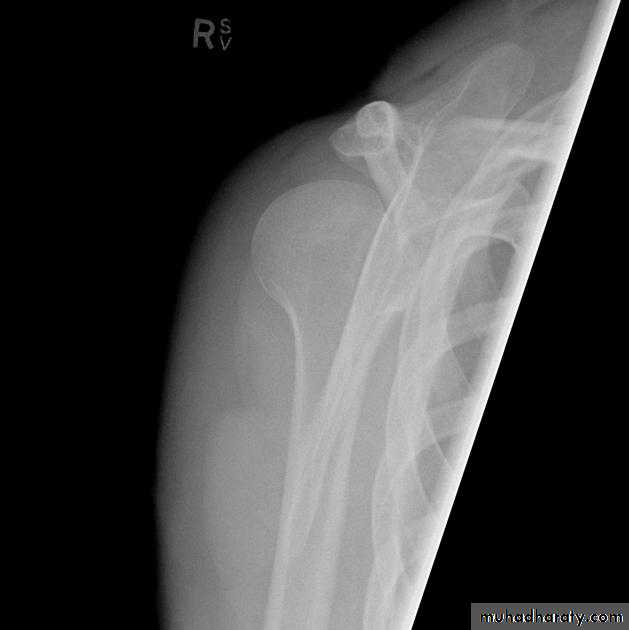

Posterior shoulder dislocation:

* very rare & form about 2-4% of shoulder dislocation.* Posterior dislocation may be missed initially on frontal radiographs in 50% of cases, as the humeral head appears to be almost normally aligned with the glenoid.

*the internally rotated humeral head takes on a rounded appearance known as the light bulb sign.

*may be associated with posterior glenoid rim or lesser tuberosity.